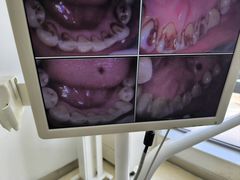

• 圣贝口腔(海淀店)

• -圣贝口腔(海淀店)

匿名用户 | 24-05-06